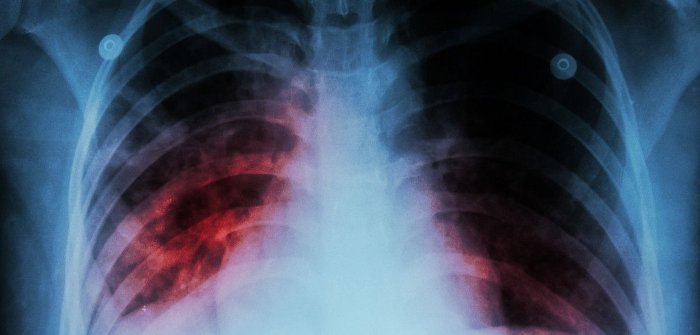

TB remains one of the world’s major killer diseases, causing TB disease in 9.6 million people and 1.5 million deaths in 2014. The only available vaccine, Bacillus Calmette-Guérin (BCG), works well (estimated 50% effective) to prevent severe disease in children but is very variable (0% to 80% effective) in how well it protects against lung disease, particularly in countries where TB is most common.